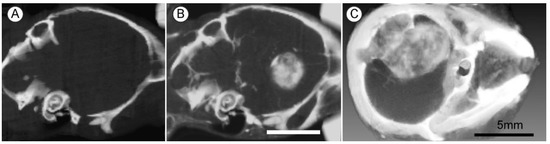

To achieve an even longer blood half-life to obtain better tumor to non-tumor effects, 11 nm AuNPs were constructed with a PEG coating (AuroVistTM), having a blood half-life of 24 h, and used to treat a challenging orthotopic highly malignant advanced glioma, (Tu2449), syngeneic for B6C3F1 mice. Fifteen hours after IV injection of 4 g Au/kg, the tumor-to-normal brain ratio was 18.8:1, and tumor concentration was 1.5% w/w gold. This level of uptake and normal brain tissue clearance produced clear X-ray images of the tumors with low non-tumor levels (Figure 5).

Figure 5. Live mouse microCT images of gliomas 9 days post implantation. (A,B) Same mouse before (A) and 15 h after (B) intravenous (IV) injection (4 g Au/kg); (C) Larger tumor imaged 15 h after IV injection of 1.7 g Au/kg. X-ray source was 45 kVp. Bars (B,C) = 5 mm.